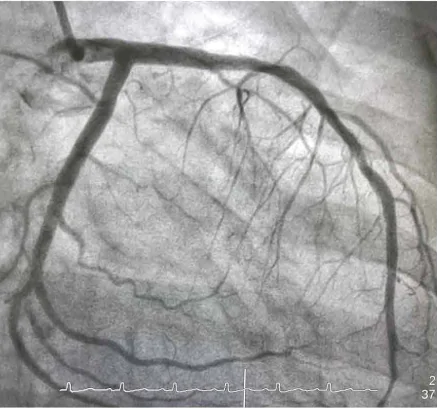

Hình 6.4 cho thấy hình ảnh chụp X-quang rất sắc nét của động mạch vành. Độ sắc nét của hình ảnh phụ thuộc rất nhiều vào độ rộng của chùm tia X.

Hình 6.4. Hình ảnh X-quang của động mạch vành